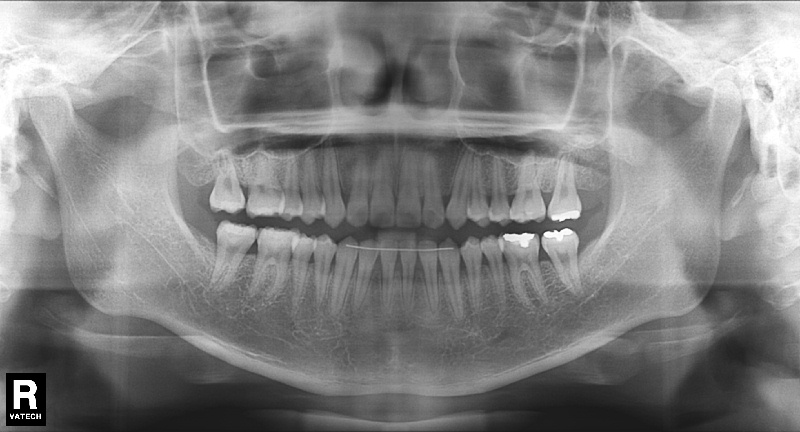

치료 전 사진입니다.